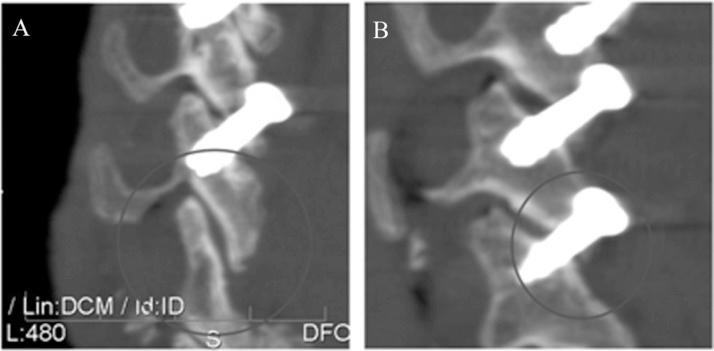

利用先前确定的关节突形态测量法来确定下颈椎经关节突螺钉置入的理想轨迹。开发了一种独特的瞄准导向器,以允许在无侧位透视荧光镜检查引导的情况下将克氏针以90°穿过关节突关节。在7个尸体标本中经皮放置克氏针和空心螺钉。器械置入完全在改良前后位透视荧光镜检查下进行。由2名接受过专科培训的骨科脊柱外科医生使用计算机断层扫描对所有标本的螺钉置入情况进行评估,以确定是否可接受。通过开放解剖来确认影像学解释。可接受的置入定义为螺钉穿过关节突关节,在下关节突和上关节突获得锚定,且不侵犯关键结构。位置不当定义为侵犯横突孔、椎管或神经根或固定不充分。

结果

共置入48枚螺钉。45枚螺钉的置入是可接受的。3例螺钉位置不当的情况包括1例关节突骨折、1例关节突分离,以及在1例C7上关节突较小的标本中1枚C6 - 7螺钉接触C7神经根。

结论

我们的数据表明,采用适当的影像学技术和瞄准导向器,在靶向阶段无需侧位透视荧光镜检查即可安全地在C3 - 7置入经皮经关节突螺钉。然而,由于C7侧块形态测量的变异性,在C6 - 7置入经关节突螺钉时必须小心。